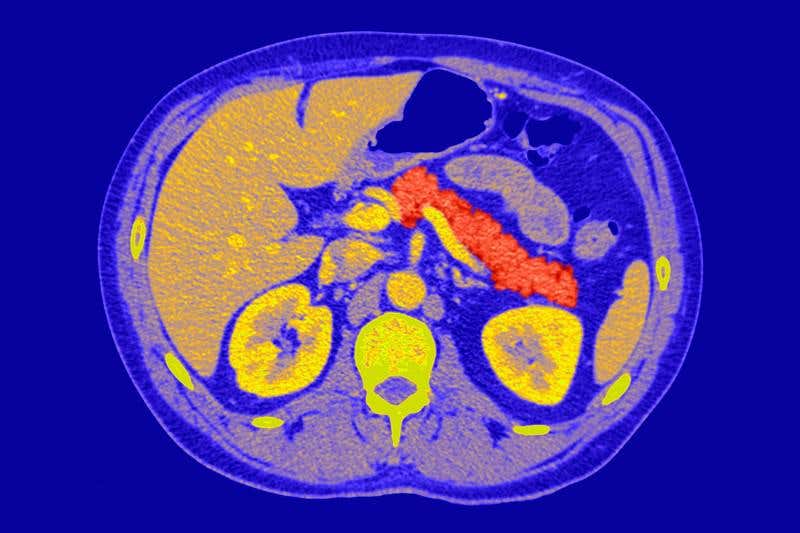

Image credit: Pr Michel Brauner/ISM/Science Photo Library